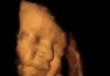

جنين يبتسم فى بطن أمه قبل ولادته بأسابيع